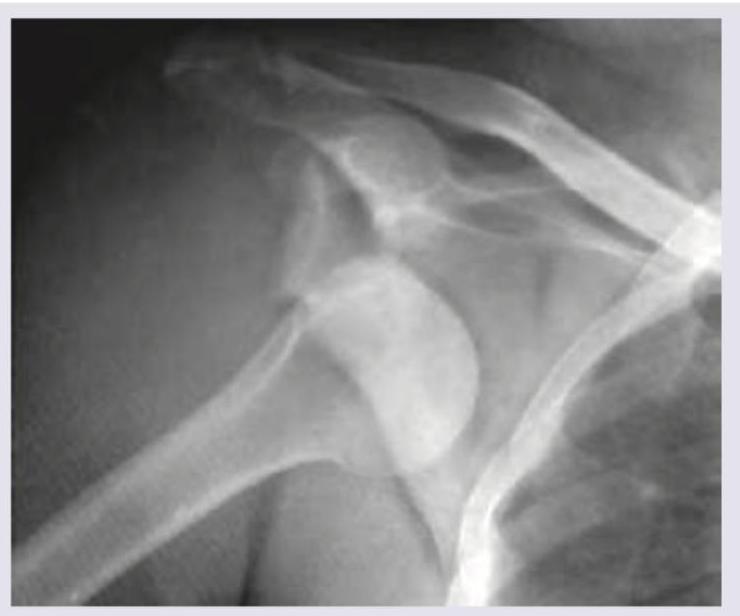

What is correct about the finding in X-ray shoulder?

Explanation: ***AP shoulder view with anterior dislocation*** - The humeral head is displaced **inferiorly and medially** relative to the glenoid, which is the characteristic finding of **anterior shoulder dislocation** on an AP radiograph - Anterior dislocations account for **95% of all shoulder dislocations** and typically result from a fall on an outstretched arm with the shoulder in abduction and external rotation - The AP view clearly shows loss of normal glenohumeral articulation with the humeral head positioned **anterior and inferior** to the glenoid fossa *AP shoulder view with posterior dislocation* - Posterior dislocations show the humeral head fixed in **internal rotation** with the characteristic **"light bulb" sign** (symmetric rounded appearance) - The humeral head typically appears **medially positioned** but not inferiorly displaced as seen in anterior dislocations - This represents only 2-5% of shoulder dislocations and is often associated with seizures or electrocution *Lateral view with anterior dislocation of shoulder* - This is an **AP view**, not a lateral view - A lateral view (Y-scapular view) would show the scapula in a **Y-shaped configuration** with the humeral head positioned anterior to the glenoid in cases of anterior dislocation - The lateral view is useful for confirming the direction of dislocation seen on AP radiographs *Lateral view with posterior dislocation of shoulder* - This is an **AP view**, not a lateral view - On a true lateral (Y-scapular) view, posterior dislocation would show the humeral head displaced **posteriorly** relative to the glenoid - Posterior dislocations are frequently missed on AP views alone, making lateral views essential for complete evaluation